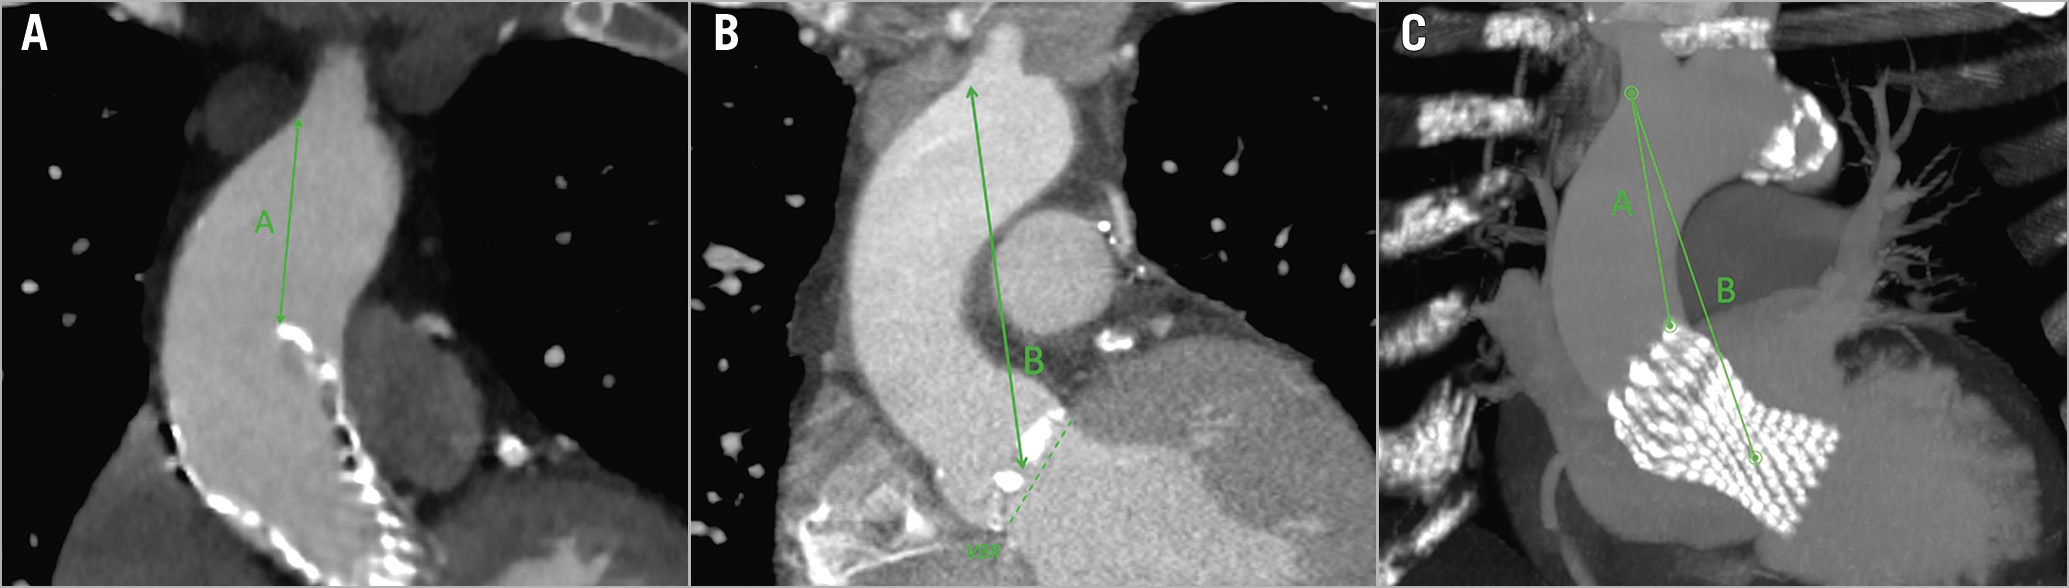

Four principal measurements were evaluated (Table 1): 1) the shortest distance between the THV and the most inferior point of the innominate artery (Figure 1, green A); 2) the shortest distance between the centre of the virtual basal ring (VBR) and the most inferior point of the innominate artery ostium (Figure 1, green B); 3) the minimal distance between the sinotubular junction (STJ) and the first THV-free anterior aortic wall point (Figure 2, green C); and 4) the maximum gap between the anterior ascending aortic wall and the upper margin of the THV stent frame (Figure 2, green D). The aim of analysing these specific measures relies mostly on two aspects, for A+B and C+D distances, respectively: first, of having enough comfort space for the positioning of the surgical ascending aortic clamp, avoiding the innominate artery ostium and the THV stent below the aortic wall; and second, of performing a safe aortotomy by scalpel without the risk of becoming entangled with the TAVI upper stent.

Figure 1. CT-scan reconstruction showing measures for aortic cross-clamping. Post-TAVI CT-scan reconstruction, showing the measures for the correct positioning of the aortic clamp, both in a 2D image (A, on the left, post-TAVI acquisition; B, in the middle, pre-TAVI acquisition) and in 3D MIP reconstruction (C, on the right): the shortest distance between the distal part of the THV stent and the inferior point of the innominate artery ostium (green A); and the shortest distance between the centre of the VBR and the inferior point of the innominate artery ostium (green B). 2D: two-dimensional; 3D: three-dimensional; CT: computed tomography; MIP: maximum intensity projection; TAVI: transcatheter aortic valve implantation; THV: transcatheter heart valve; VBR: virtual basal ring